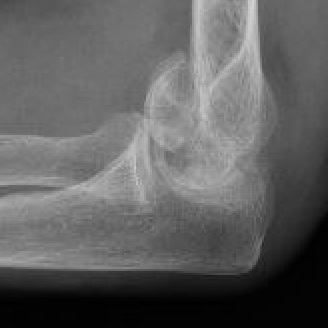

- nerve palsies 2%, non-union 1.5%, infection 1%

Heller et al J Hand Surg Am 2025

- systematic review of complications after capitellum fixation

- elbow pain 21%

- radiocapitellar arthritis 19%

- hardware removal 17%

- HO 13%

cap hocap hocap ho